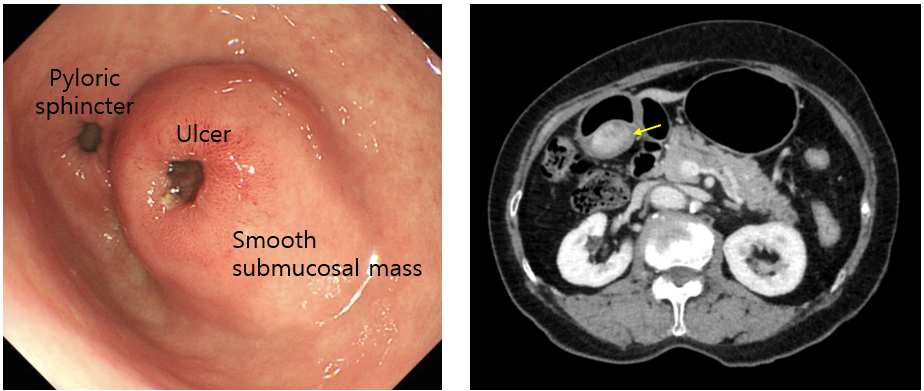

45세 남자가 5일 전부터 식사 후에 배가 아파서 병원에 왔다. 3년 전부터 속쓰림과 윗배 통증이 있어서 간헐적으로 제산제를 복용해왔다. 혈압 125/82 mmHg, 맥박 82회/분, 호흡 18회/분, 체온 36.7℃이다. 배는 편평하고 부드러우며 압통과 반동압통은 없다. 위내시경 사진과 복부 컴퓨터 단층촬영 사진이다. 내시경 조직검사에서 방추세포 증식 (spindle cell proliferation)이 보이고 복부 컴퓨터단층촬영에서 커진 림프절과 다른 장기에 전이는 없다. 치료는?

Img | CT: Subepithelial mass at distal stomach, without LN/distant metastasis |

Etc | EGD: Pyloric canal protruding mass, with central ulceration EGD Bx: Spindle cell proliferation |

Imp: 위장관기질종양(gastrointestinal stromal tumor, GIST)

• 이에 시행한 EGD상 매끈하게 내강으로 돌출된 mass가 보이며, mass에 central ulceration이 보인다. 이렇게 매끈한 mass의 경우 GIST를 우선적으로 의심해볼 수 있다.

• 따라서 확진을 위해 조직검사를 시행했고, GIST의 병리학적 특성인 spindle cell proliferation이 관찰된다.

• GIST 확진 후 전이 여부 등을 확인하기 위해 촬영한 복부 CT상 전이는 없다. 참고로 CT상 mass가 epithelium 아래에 자리한 것을 볼 수 있으며, 이 역시 GIST의 특징적 영상소견이다.